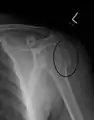

A fracture of the greater tuberosity as seen on AP X ray

A fracture of the greater tuberosity of the humerus